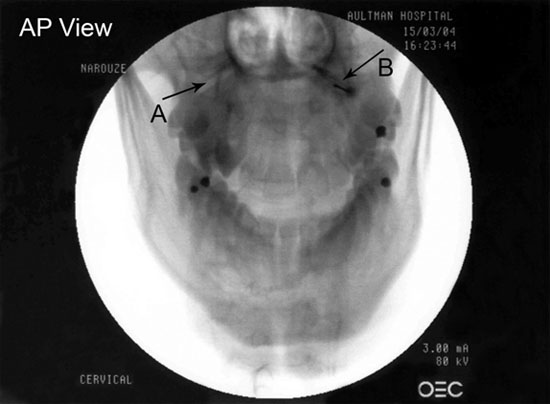

The C2 dorsal root ganglion and nerve root with its surrounding dural sleeve crosses the posterior aspect of the middle of the joint. Therefore, during atlanto-axial joint injection, the needle should be directed toward the posterolateral aspect of the joint. This will avoid injury to the C2 nerve root medially or the vertebral artery laterally (Figures 3-5).[12][17]

Figure 3. AP view showing the needle in a tunnel view inside the lateral part of the lateral AA joint.

Figure 4. AP view showing the lateral atlanto-axial joint (A) and the needle tip and contrast agent within the lateral AA joint (B).